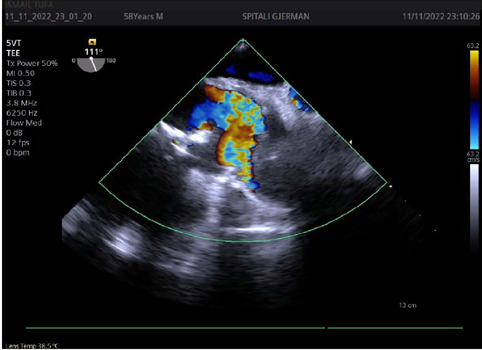

A 58-year-old man, who has undergone ascending aorta replacement, started to complain of pain in the lower limbs, shortness of breath, and progressive fatigue a few months after surgery. Transthoracic and transesophageal Doppler echocardiographies revealed a diseased bicuspid aortic valve and a subocclusive mass in the ascending aorta. Thoracic computed tomography angiography confirmed the presence of a subocclusive mass, pseudoaneurysm formation, and a distorted shape of the Dacron® graft. The patient underwent urgent surgery to remove the mass, which appeared to be a thrombus, and aortic valve and ascending aorta replacement. Kinking of vascular graft has been reported including surgical techniques to correct the excessive length to avoid gradients and guarantee laminar flow. When kinking is severe, high gradients and hemolysis can be detected. However, thrombus formation in the ascending aorta segment is less likely, due to the high blood velocity flow. Therefore, several concurrent causes should be considered. In this case, the most probable explanation for thrombus formation was kinking of a too long Dacron® graft, combined with extrinsic compression effect of the graft by the pseudoaneurysm at the anastomosis site and anomalous flow directed from the diseased bicuspid aortic valve. Various grades of Dacron® graft kinking might occur following ascending aorta replacement and undiagnosed at follow-up especially if resulting in mild symptoms, thus, careful visual and echocardiography evaluation should be done at the end of surgery. Finally, distorted Dacron® graft might trigger thrombus formation when inflammation and coagulation processes are set off during bacteria or viral infection.

Abstract Image